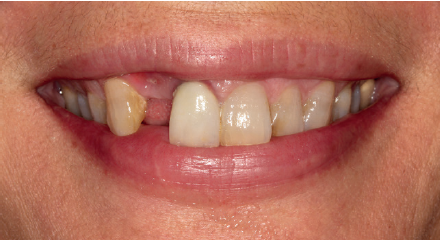

Se presenta el caso de una mujer de 36 años que acude a la consulta demandando solución para un implante situado en la posición 1.2. Este implante ha llevado una rehabilitación con una corona durante un corto período de tiempo en el que se produjo una mucositis importante y una pérdida del grosor del tejido gingival, por lo que la corona fue retirada.

La paciente presenta un provisional removible y el tejido blando circundante a la zona de la emergencia inicial de la prótesis implantosoportada se encuentra en malas condiciones, con una pérdida de grosor importante y los restos de una fístula de tejido blando (Figuras 1-4).